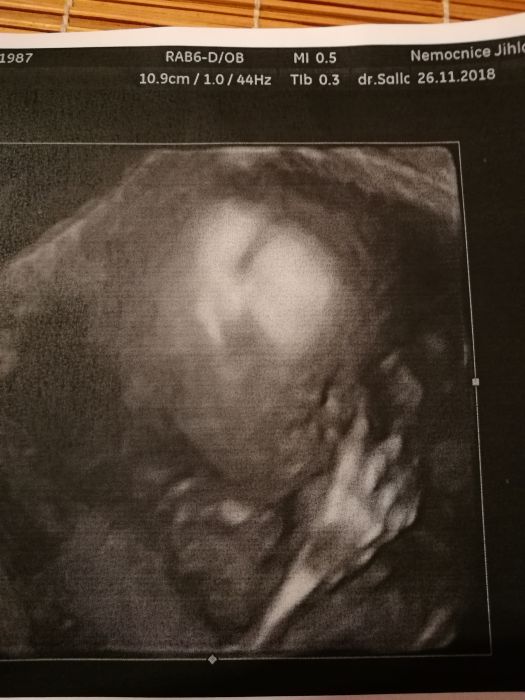

Holky, dopadli jsme na jednicku. Vypada to fakt na tu holcicku, tak mame radost. Krasne nam roste s vse ma v poradku, velikosti je dokonce o den napred. Vaha cca 400g. V pondeli jdeme na srdicko a posledni screening mame 30.1.19. Fotky nejake mam, tak vam je sem potom taky hodim.